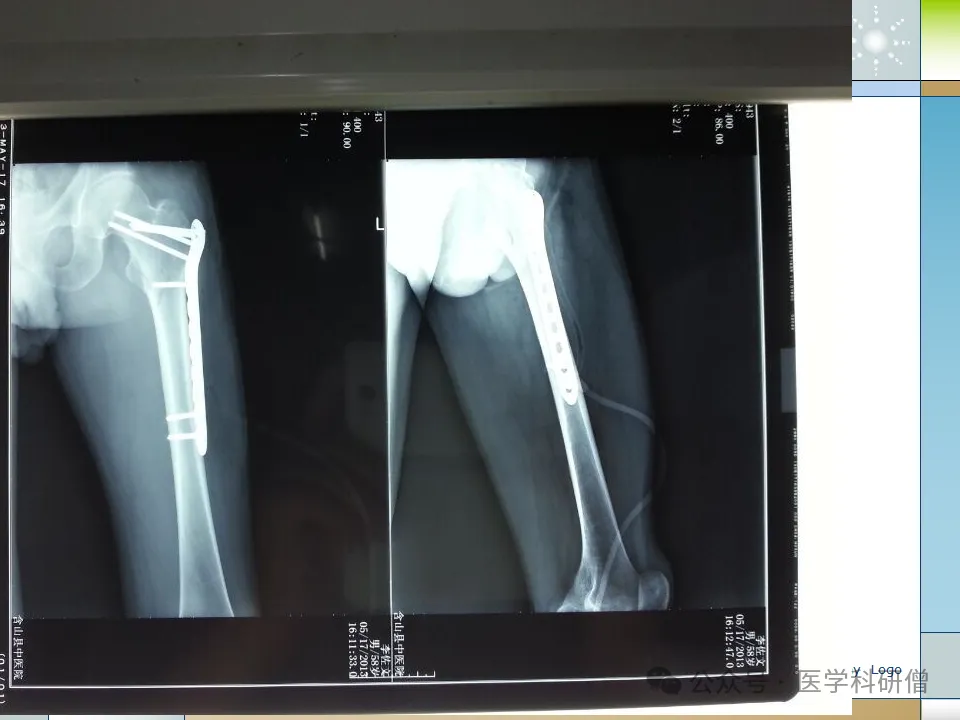

1. 动力髋镙钉(DHS)

动力髋镙钉是一种常用的内固定方法,适用于稳定型股骨粗隆间骨折。其优点是具有强固定作用,能够避免钉端穿透股骨头,减少不愈合的风险。然而,DHS的抗旋能力较差,术中骨膜损伤较大,且在固定时需要开槽,可能破坏股骨头的血供。

8. 解剖钢板及LISS解剖钢板

解剖钢板和LISS解剖钢板是根据股骨近端的解剖形态设计的内固定物。解剖钢板能够与股骨近端解剖相吻合,提供抗剪切力、旋转力和弯曲力的强大支撑。LISS钢板固定则是一种微创固定系统,适用于骨质疏松患者和假体周围骨折。这两种内固定方法具有操作简便、固定可靠等优点。